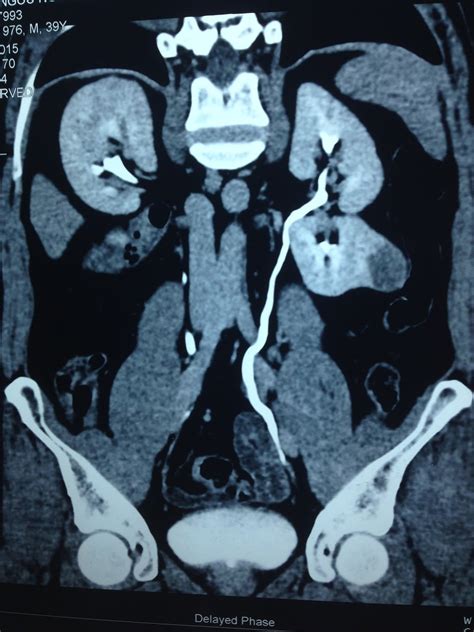

A Kidney AML tumor is a type of mesenchymal tumor, which means it arises from the soft tissues of the kidney rather than the filtering units themselves. Because these tumors contain fat, they have a unique appearance on medical imaging tests like CT scans or MRIs, which helps radiologists distinguish them from potentially cancerous kidney tumors. Most angiomyolipomas occur sporadically, meaning they appear spontaneously without a clear hereditary link. However, a significant subset of patients develops these tumors in association with a genetic disorder known as Tuberous Sclerosis Complex (TSC). In patients with TSC, these tumors are often more numerous, larger, and more likely to affect both kidneys.

Diagnosing a Kidney AML tumor involves various imaging modalities to assess the size and character of the lesion. A CT scan with contrast or an MRI is typically the gold standard because these scans can identify the presence of fat within the tumor—a hallmark characteristic of an angiomyolipoma.